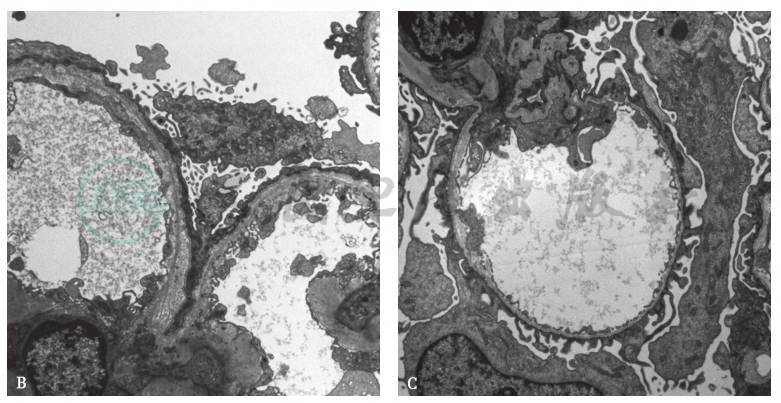

典型者呈弥漫肾小球基底膜(GBM)厚薄不均、分层、网篮样改变(图1B),极少数可见GBM断裂,多数XLAS男性、ARAS患者及少数XLAS女性表现为典型改变,部分儿童、XLAS女性和ADAS患者可表现为弥漫GBM变薄(图1C)。

图1 Alport综合征肾脏病理表现

A.光镜下肾间质泡沫细胞(HE,200 ×);B.电镜示肾小球基底膜(GBM)厚薄不均、分层、网篮样改变(18 000 ×);C.电镜示 GBM弥漫变薄(18 000 ×)